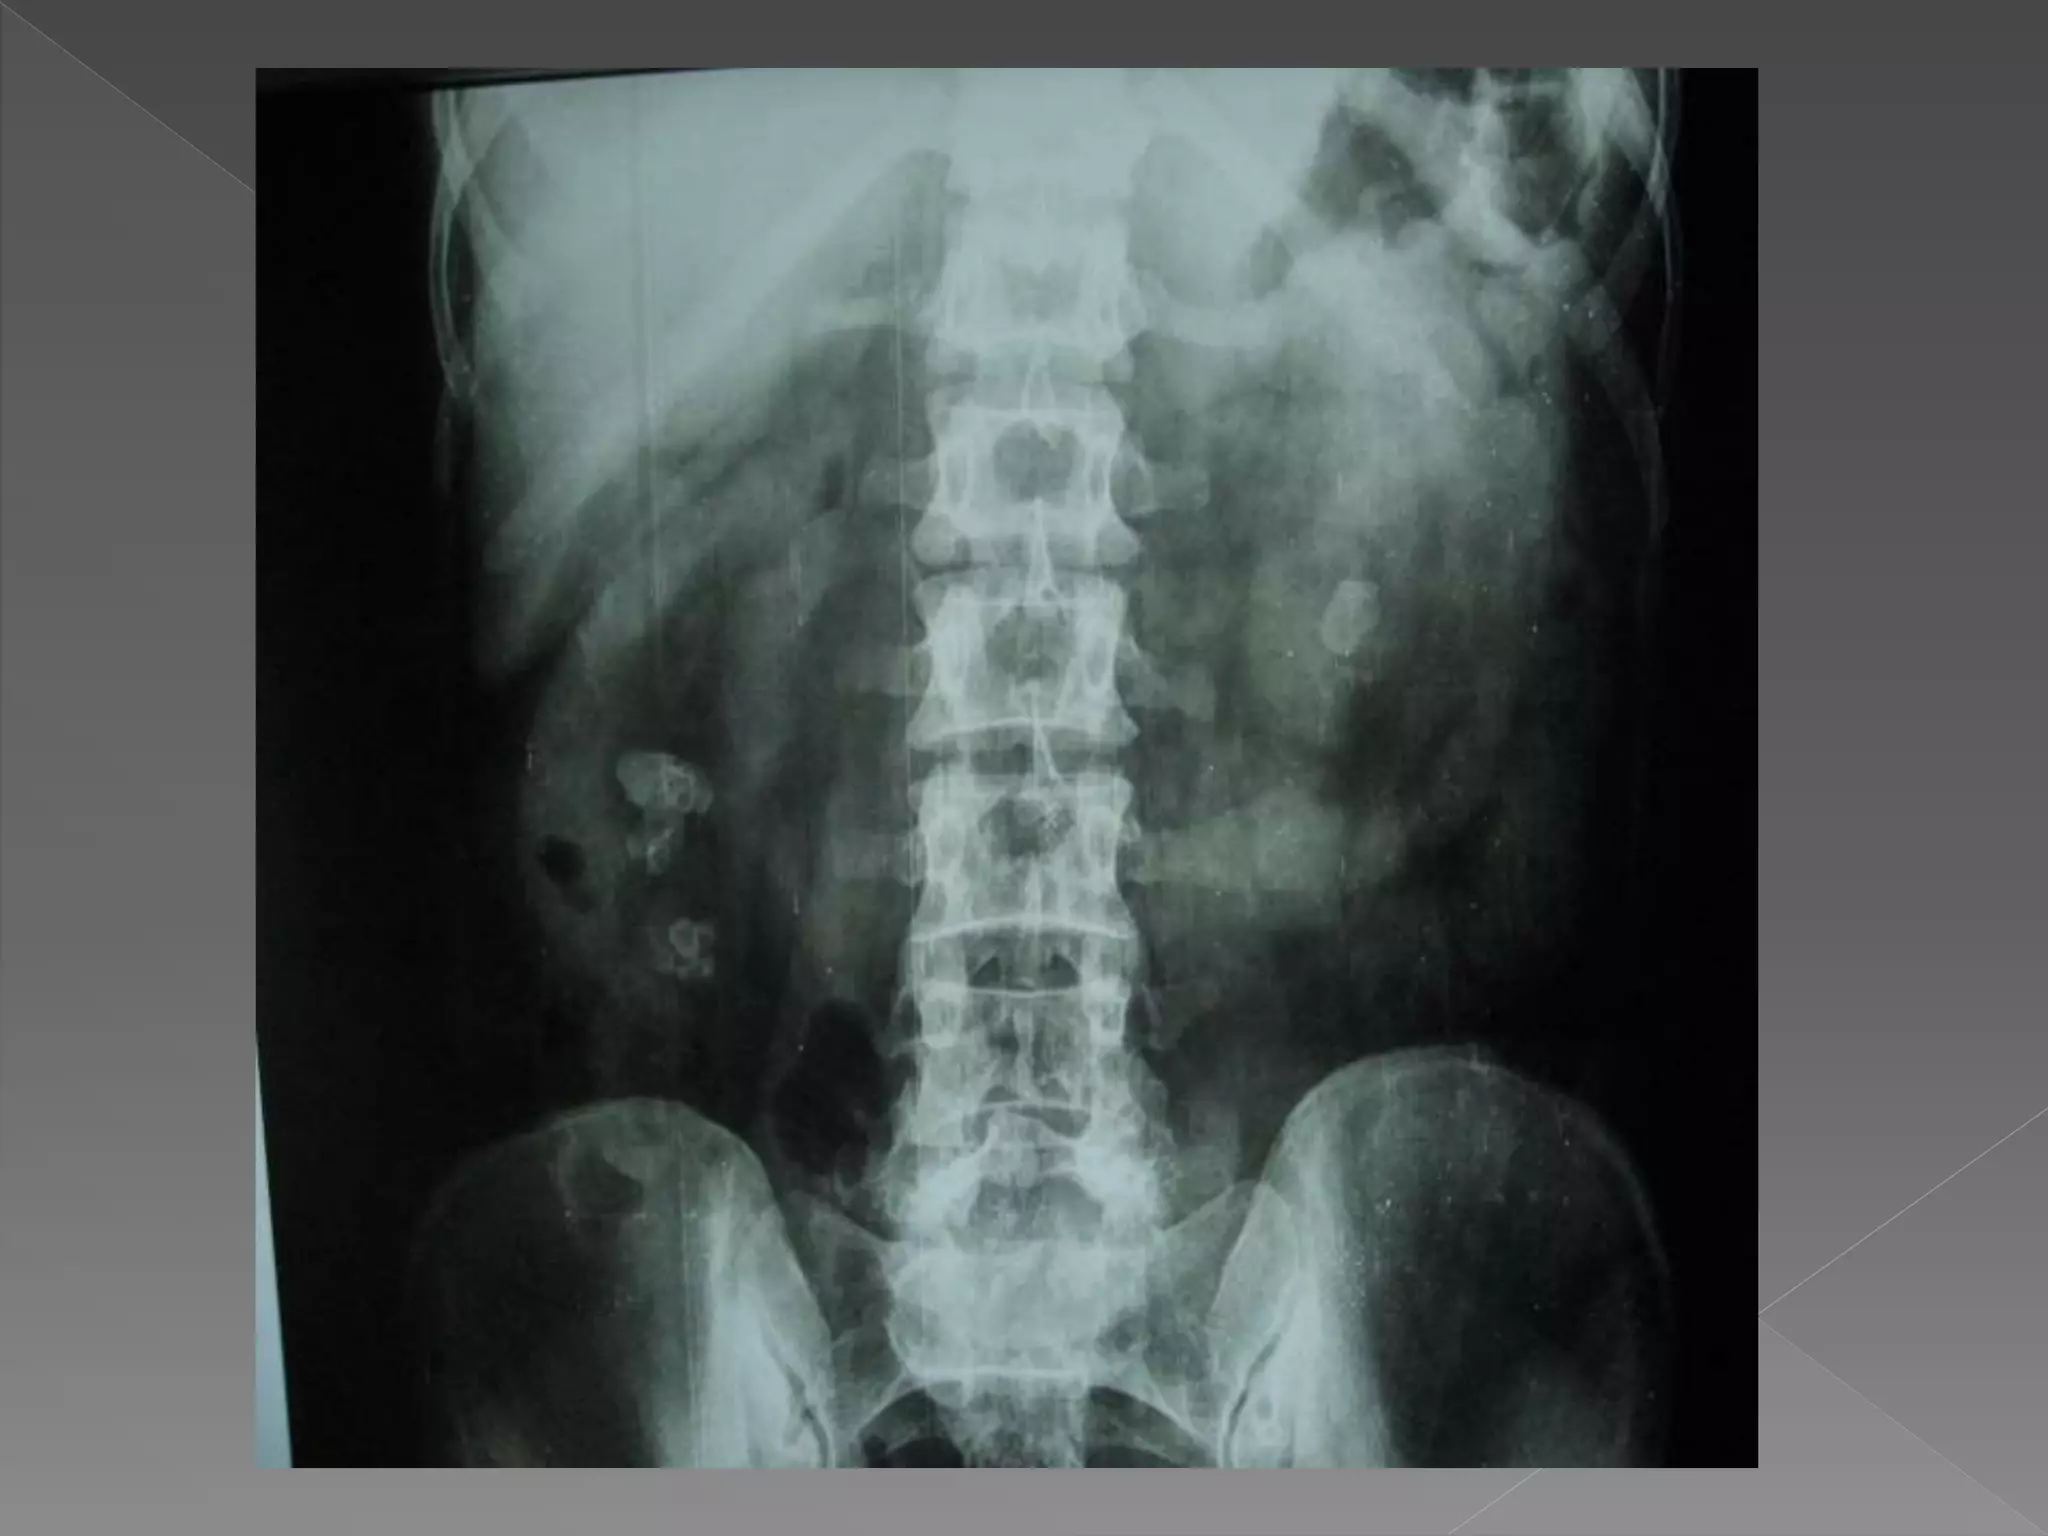

 The plain film demonstrates

 The plainfilm demonstrates calcification within distended upper pole calyces